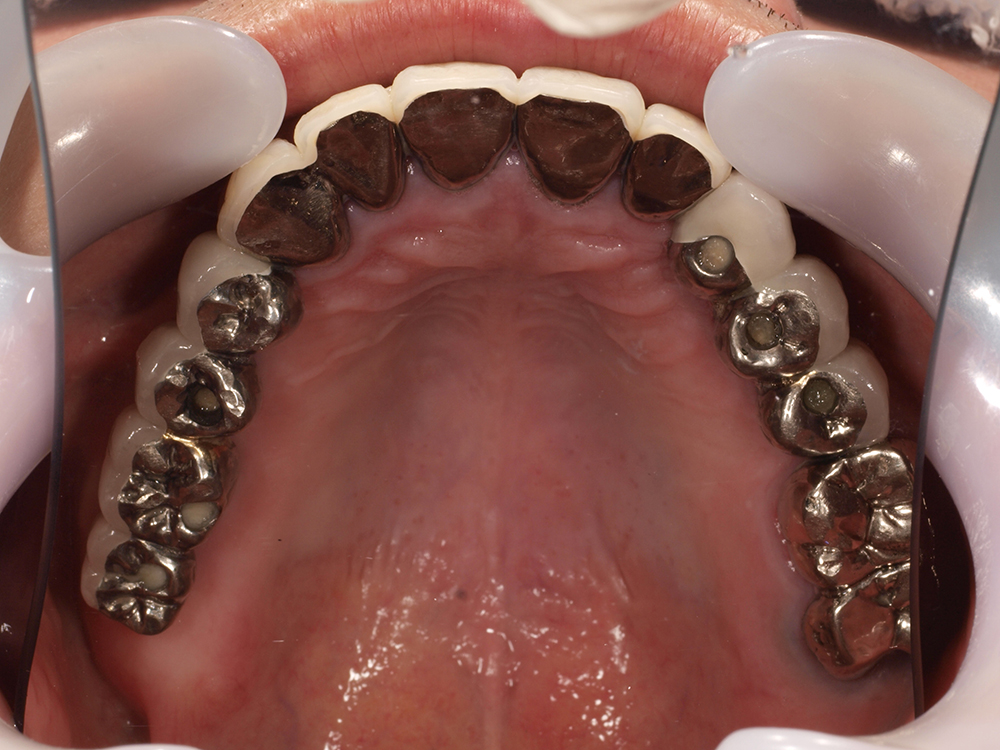

64歳 女性 紹介患者様

- 主訴

- 上下左右の歯が無くて、食べずらい、右下の歯が痛い

- 処置内容

- 右上3本、左上1本、右下3本、左下3本、鎮静麻酔

- 治療費用

- 上顎:約180万円(税込)下顎:約170万円(税込)

- 治療期間

- 上顎:約9か月、下顎:約6か月

- リスク

-

術後の腫れ、痛み(ピークは3日後、1週間で軽減)

上部構造物、仮歯の破折、人工歯根脱落リスクがあります